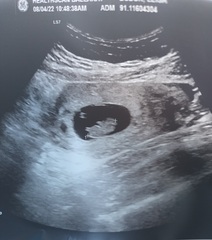

Had an ultrasound this morning, all looks perfect! 9 weeks. Cute little blobby.

Ah boo I don't know why the pic posted twice...

@ALittleBitofVitriol Aww hi little one 😍 So glad your scan went well!